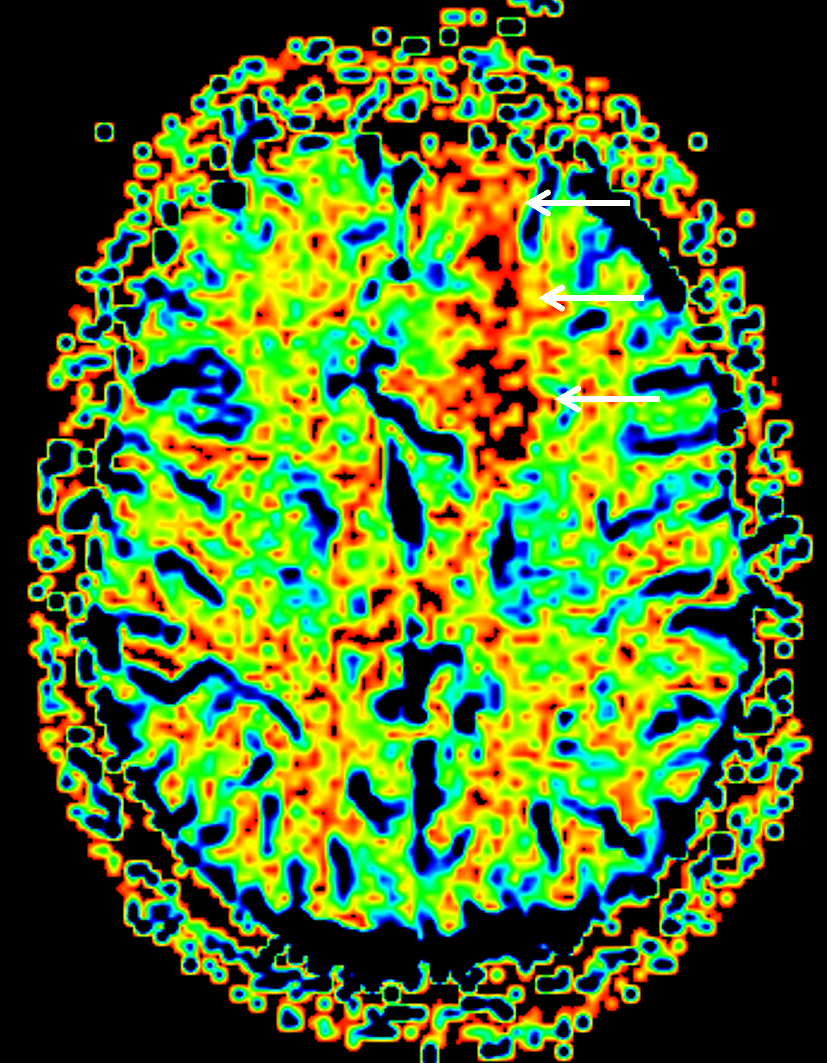

Cerebral blood volume map demonstrates relatively elevated cerebral blood volume corresponding to the left frontal mass (white arrows).